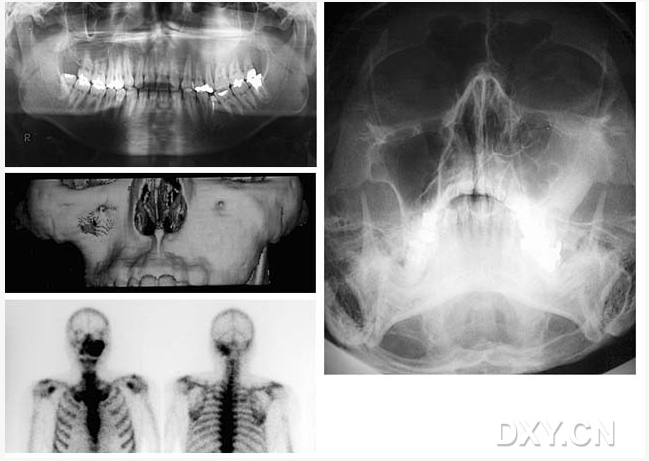

成釉細胞瘤

骨肉瘤

頜骨纖維性結(jié)構(gòu)不良癥

舍格倫綜合征

大理石骨?。ㄏ骂M骨有明顯的骨化影像,恒牙埋伏)

鼻竇炎(注意不要誤診呀)